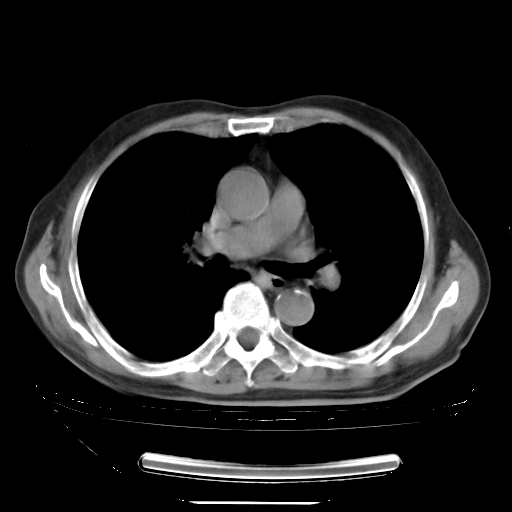

胸腹部CT,诊断意见:左上肺叶钙化灶、左侧胸膜局限性增厚并钙化、胆囊炎。描述部分肺组织呈磨玻璃样改变。